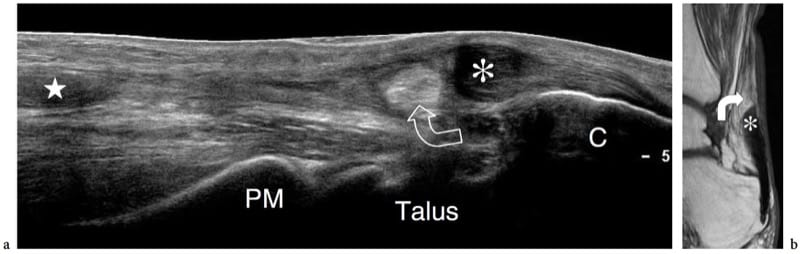

Visualización en campo externo

Uno de los defectos que puede tener la ecografía es el poco campo de visión. Se acentúa en el momento de usar sondas lineales. La visualización en campo extendido permite aumentar el campo de visión realizando una imagen panorámica de la zona a estudiar. Se puede realizar con cualquier transductor y es necesario un software apropiado